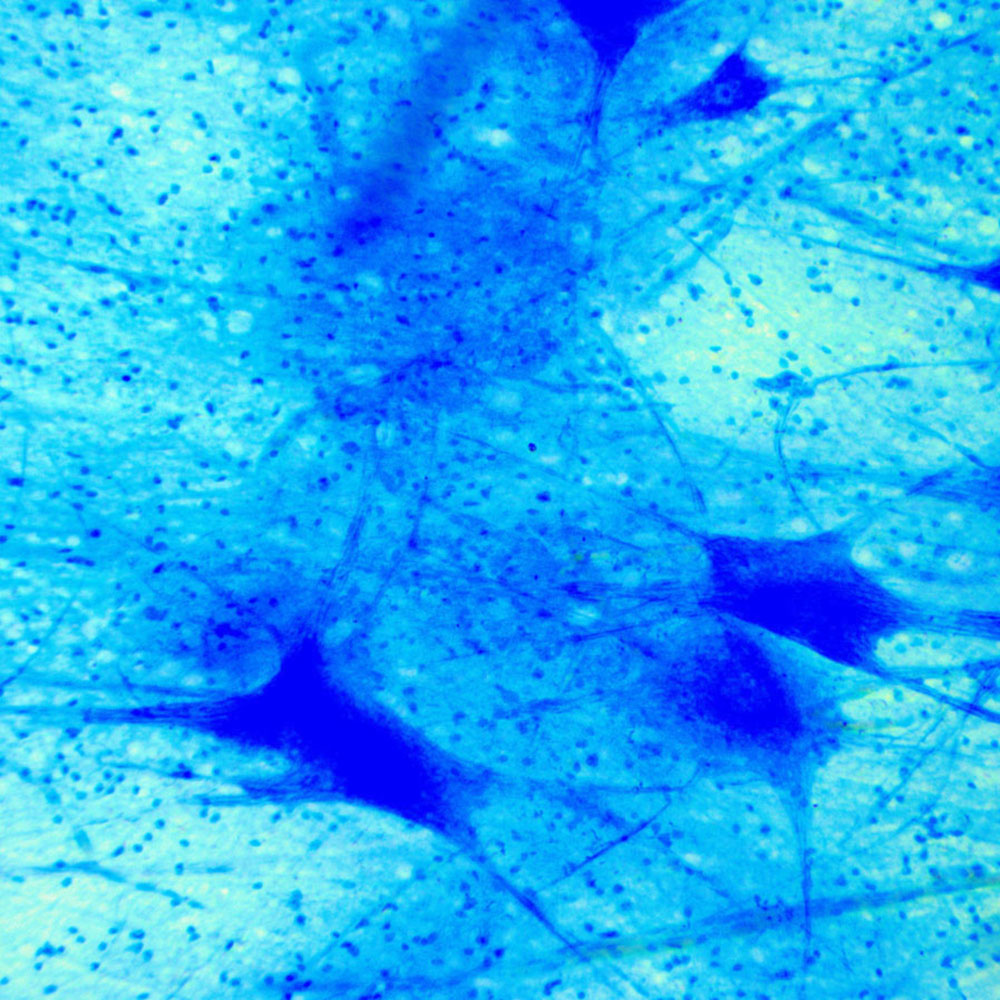

Мікроскоп Delta Optical GENETIC PRO BINO 40x-1000x — це універсальний інструмент, який оцінять як професіонали, так і любителі досліджень мікросвіту. Здебільшого він використовується для серйозних медичних, ветеринарних та біологічних досліджень, а також для навчання в студентських лабораторіях і школах. Подекуди його обирають люди, які вивчають таємниці мікросвіту для власного задоволення, але підходять до процесу амбітно та потребують надійного обладнання. Вагомою перевагою даної моделі є вдале співвідношення ціни і якості.

Міцна металева конструкція та відмінна ергономіка гарантують тривалу і комфортну експлуатацію. Бінокулярна насадка дозволяє досліджувати зразки двома очима одночасно, завдяки чому мінімізує напруження зору. Насадка обертається на 360 градусів, а 30-градусний нахил її окулярних тубусів сприяє комфорту при тривалій роботі в положенні сидячи. Оптика мікроскопа характеризується високою якістю, ахроматичністю та наявністю просвітлюючого покриття. У 4-х позиційній револьверній головці встановлені об'єктиви стандарту DIN: 4x, 10x, 40x, 100х. У комплекті також поставляється пара ширококутних 10-кратних окулярів з полем зору 18 мм. Можливі збільшення мікроскопа в такій комплектації складають 40х, 100х, 400х, 1000х. Придбавши окремо 16-кратні окуляри можливо підвищити збільшення до 1600х.

Дана модель оснащена яскравою світлодіодною нижньою підсвіткою і призначена для спостереження методом світлого поля в прохідному світлі. Важливою частиною освітлювальної системи є конденсор Аббе з ірисовою діафрагмою та фільтротримачем.